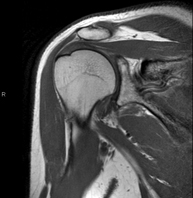

RM d'Espatlla

RM d'EspatllaExploració per a l'estudi de lesions en els tendons, els músculs i les articulacions. La seva principal utilitat resideix en diagnosticar les lesions dels tendons del braçal rotatori. Té una durada aproximada de 20 minuts. No utilitza radiació ionitzant.